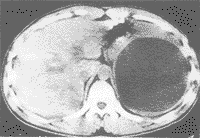

脾囊腫的診斷常常依賴於影像學檢查。脾包蟲性囊腫主要發生在我國北方牧區,依據病史及實驗室檢查、臨床診斷通常並不困難。脾臟表皮樣囊腫患者大多無臨床症狀,常因健康體檢或在其他疾病進行檢查時偶然發現。少數患者就診時發現腹部腫塊,觸之緊張,可有痛感,略有彈性,可活動,吸氣時也可移位。B超、CT或選擇性脾動脈造影等均能較正確的協助診斷,但有時需要剖腹探查證實。